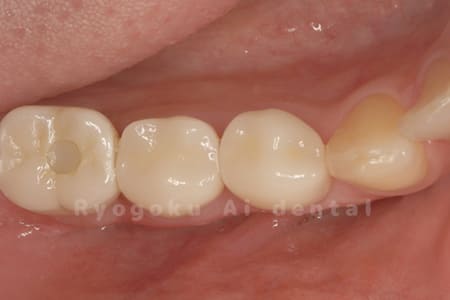

Case11

- 治療内容

- セラミッククラウン、セラミックインレー

-

- 治療費用

- 123,000円×2(セラミッククラン)、77,000円(セラミックインレー)

銀歯が取れて、ご来院された患者様です。奥歯2本をセラミッククラウン、手前の小臼歯をセラミックインレーで治療を行いました。

<リスク・副作用>

過度の咬合や衝撃で割れることがあります。